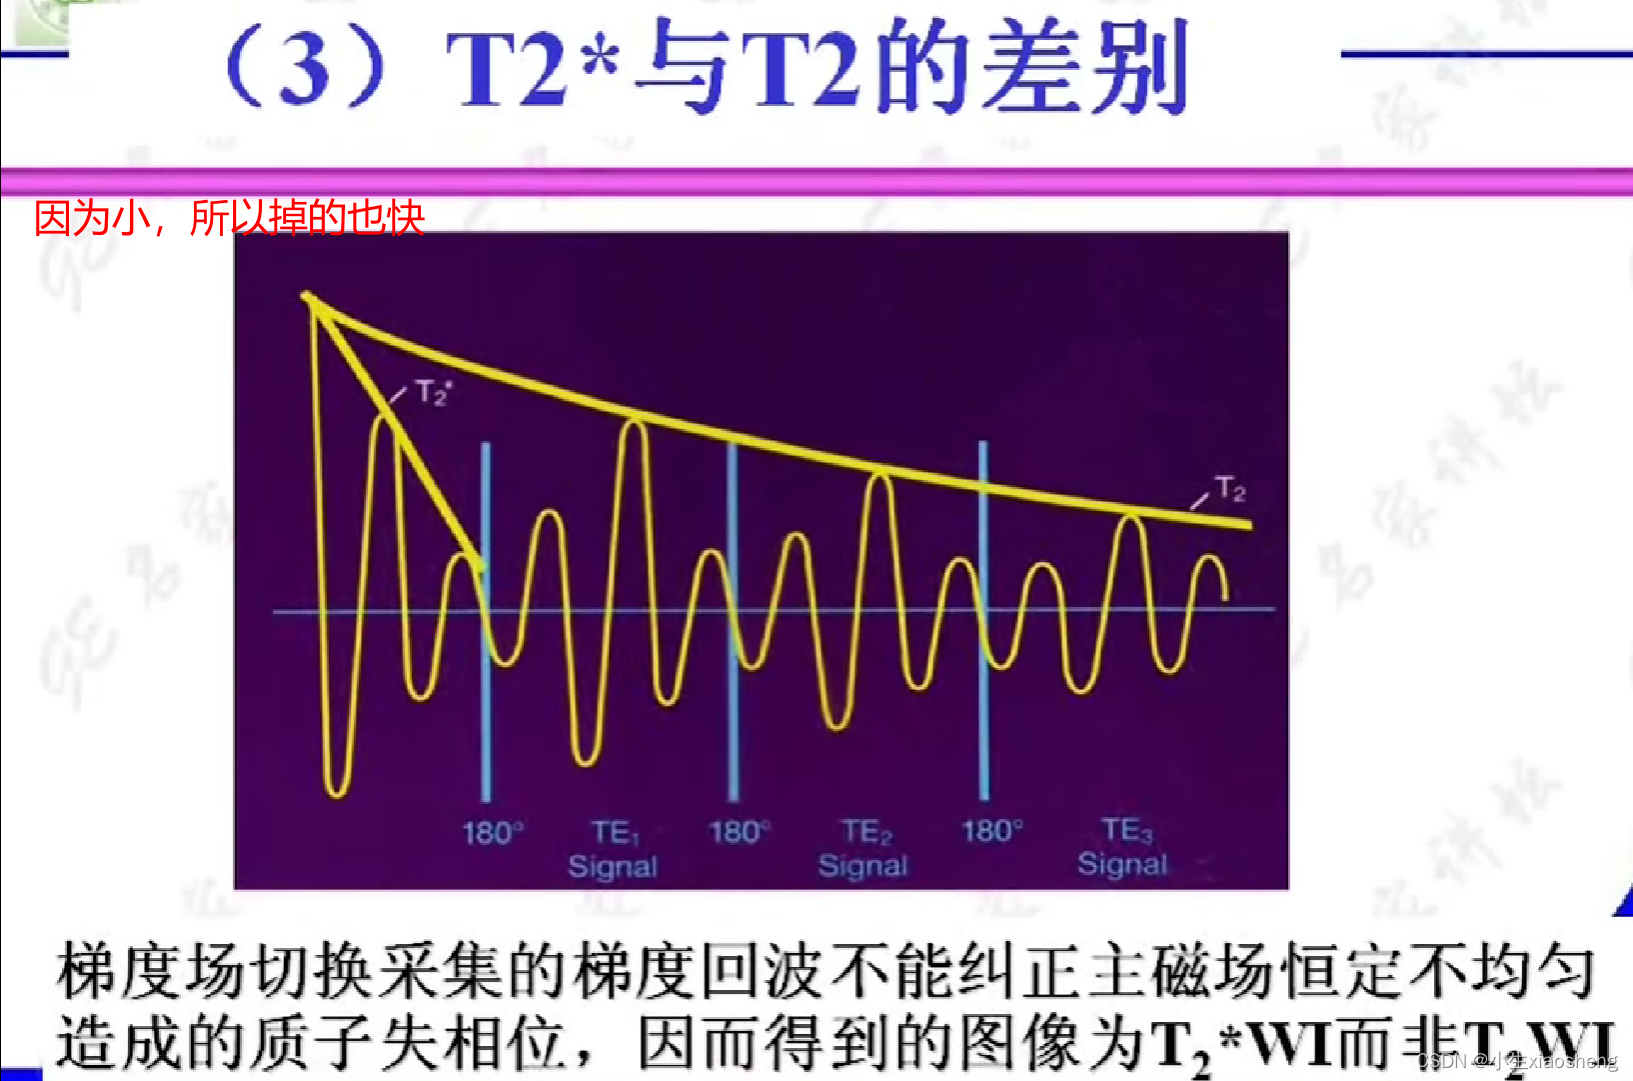

五、梯度回波类序列

GRE就是梯度回波